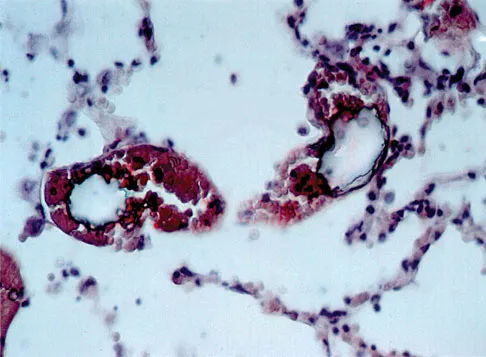

Figure 49 shows a histologic section of the lung in a patient who died during total hip arthroplasty. What unexpected finding is seen in the pulmonary capillaries?

Explanation

Embolic material generated during total knee arthroplasty (TKA) shown in Figure 29 is composed of which of the following substances?

Explanation